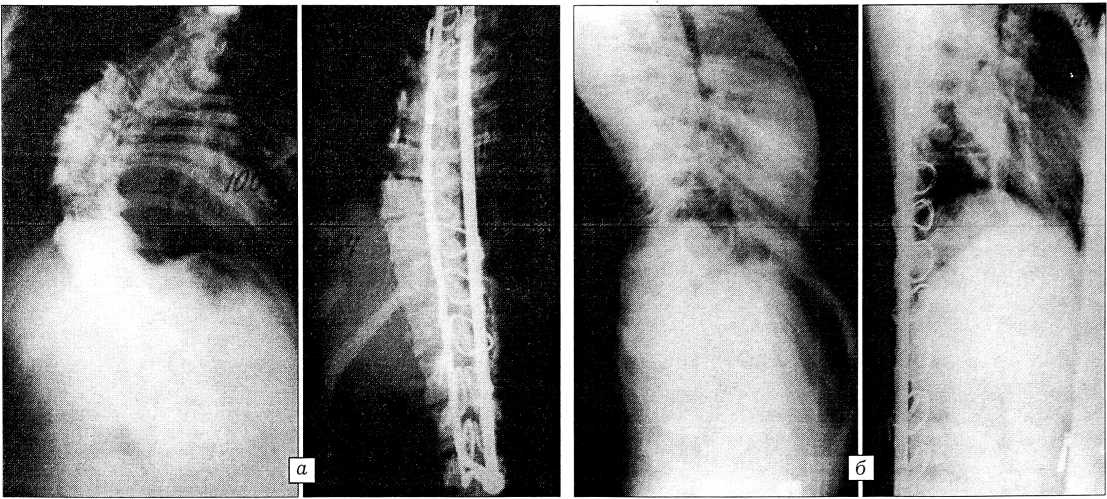

Как видно из табл. 3, средняя коррекция деформации при разных вариантах операций с применением дистрактора Харрингтона и стержня Люке существенно не различалась. При крайне тяжелом и ригидном сколиозе выполнение дискэктомии на нескольких уровнях способствовало мобилизации позвоночника и увеличению коррекции. Анализ динамики деформации в послеоперационном периоде показывает, что достигнутая коррекция частично утрачивалась во всех группах. Вероятность дальнейшего прогрессирования деформации по прогностическим признакам была наибольшей у пациентов 2-й и 3-й групп, но именно в 3-й группе отмечена наименьшая потеря достигнутой коррекции (рис. 1).

Рис. 1. Рентгенограммы больной Н. с диспластическим правосторонним грудным сколиозом IV степени до операции и после коррекции деформации дистрактором Харрингтона с поддужечной фиксацией с вогнутой стороны и стержнем Люке с выпуклой. а — прямая проекция: до операции общий угол деформации 100°, после операции коррекция общего угла 54°; б — боковая проекция: физиологические изгибы позвоночника сглажены до и после операции.